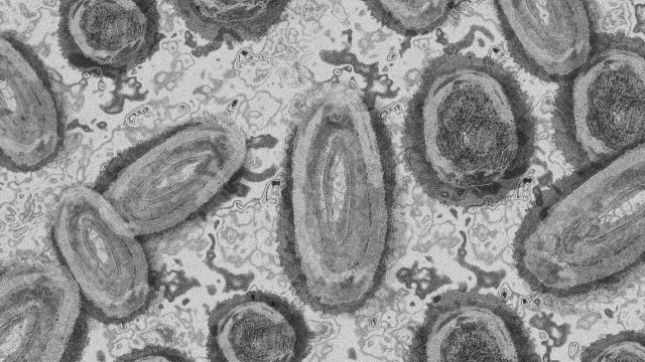

Извънредно положение в Калифорния заради маймунската шарка

Губернаторът на Калифорния Гавин Нюсъм обяви снощи извънредно положение в щата поради разпространението на маймунската шарка, за да „подкрепи усилията на щатските власти за ваксинация”, съобщи Ройтерс.

В Калифорния са потвърдени близо 800 случая на маймунска шарка, сочат официални данни от четвъртък. 98,3% от случаите са при мъже, повечето от които се идентифицират като ЛГБТ. Вирусът се разпространява предимно сред мъже, които правят секс с лица от същия пол, както и при транссексуални и лица, които не се идентифицират като жени или мъже.